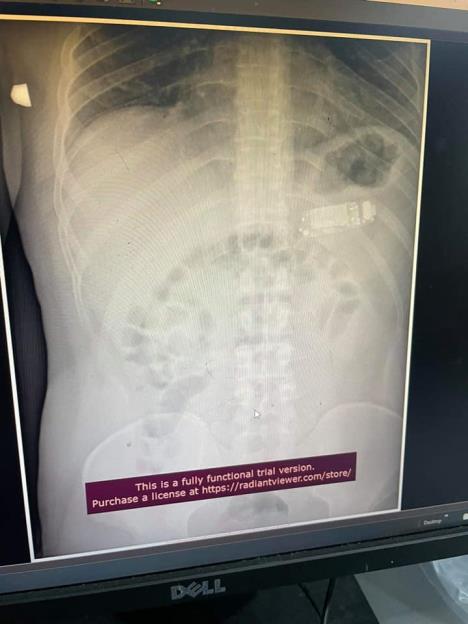

Tridesettrogodišnjak je došao u Prištinu u bolnicu žaleći se na bol u stomaku. Na rendgenskom snimku video se telefon - model s početka 2000-ih godina.

Taj stariji model je bio prevelik da bi bio svaren i ugrožavao je pacijentov život, jer je kiselina iz baterije vrlo opasna za organizam ako procuri.

Hirurg Skender Telaku vodio je medicinski tim bolnice u Prištini koji je nesrećnom muškarcu uklonio Nokiju iz želuca.

Lekar je fotogafije podelio na Fejsbuku. Telefon su uspeli da izvade endoskopijom, bez sečenja želuca. Endoskopija je metoda kojom se pregledi i manje intervencije izvršavaju instrumentom koji u telo ulazi kroz usta.